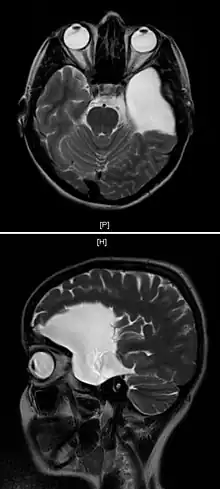

An MRI of a 25-year-old woman with left frontotemporal arachnoid cyst.

Diagnosis is principally by MRI. Frequently, arachnoid cysts are incidental findings on MRI scans performed for other clinical reasons. In practice, diagnosis of symptomatic arachnoid cysts requires symptoms to be present, and many with the disorder never develop symptoms.